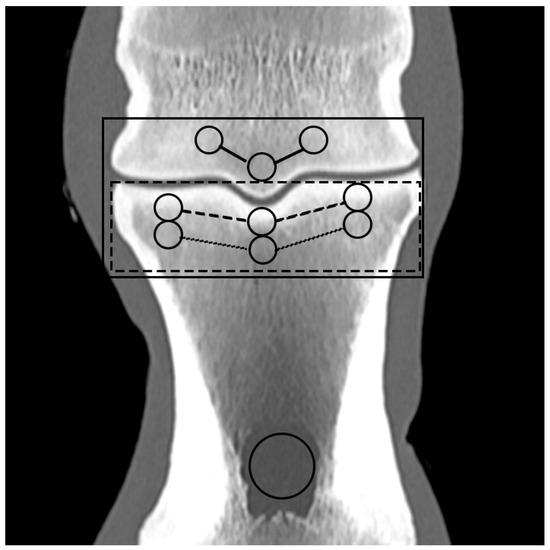

Based on the CT raw data, EAN and ED maps were created from both SSDECT and SBCT images (slice thickness 2 mm), and ROIs were drawn in the virtual monochromatic images (window level 500, window width 2500) using the proprietary software (Raw Data Analysis, CANON Medical and Intellispace Portal 12, Philips Healthcare). Mean EAN/ED values were recorded for each ROI. In total, 29 ROIs and 16 zones were defined for each distal limb. A zone referred to a certain anatomical area, and the mean EAN/ED was calculated from all ROIs included in this area. In the distal aspect of the third metacarpal (MC) and metatarsal (MT) bone, a mid-dorsal image was chosen, and one ROI each was placed in the subchondral bone of the sagittal ridge and the medial and lateral condyle, respectively (dorsal MC/MT zone) (Figure 1). Additionally, a transverse image was chosen at the level of the maximum width of the proximal sesamoid bones (PSB), i.e., at the transition from the distal to the mid-third of the PSBs, and 1 ROI each was placed in the palmar/plantar subchondral bone of the medial and lateral metacarpal/metatarsal condyle (plantar MC/MT zone) and the dorsal subchondral bone of the medial and lateral proximal sesamoid bone (PSB zone) (Figure 2). The mean of all palmar/plantar ROIs in the FJ area (plantar MC/MT and PSB ROIs) represented the palmar/plantar FJ zone (Figure 2). In the first (P1) and second (P2) phalanx, a mid-dorsal image was chosen at the level of the marrow cavity or nutrient foramen, respectively, and in the third phalanx (P3), a dorsal image was chosen parallel to the dorsal surface of the bone at the level of the solar canal. Three ROIs each (medial and lateral fovea, sagittal groove or extensor process) were drawn in the proximal subchondral bone (proximal P1/P2/P3 subchondral zone) and trabecular bone (proximal P1/P2/P3 trabecular zone) distal to the latter in all phalanges (Figure 1 and Figure 3). Larger zones were calculated including all ROIs in the proximal subchondral and trabecular bone of P1, P2 and P3, respectively (proximal epiphyseal P1/P2/P3 zone) (Figure 1 and Figure 3). Moreover, the mean of all dorsal ROIs in the FJ area (distal MC/MT, proximal P1) represented the dorsal FJ zone (Figure 1). A single ROI was also applied to the marrow cavity of P1 (Figure 1). On a mid-dorsal plane of the NB, 3 ROIs were evenly distributed medially, centrally, and laterally within the spongious bone (navicular zone) (Figure 4). All ROIs were of a circular shape with a diameter of 4 mm (smallest ROI possible for both CT units) except for the circular ROI in the marrow cavity of P1, the diameter of which was adapted to the size of the marrow cavity.

Figure 2. Regions of interest (ROIs; circles) and zones (mean EAN calculated from all ROIs included in an anatomical area; lines) in the palmar/plantar aspect of a front fetlock joint on a transverse monoenergetic image (detector-based spectral computed tomography, Philips) at the mid-level of the proximal sesamoid bones (PSBs): ROIs in the subchondral bone of the medial and lateral metacarpal/metatarsal condyle (palmar/plantar MC/MT zone; continuous line), the dorsal subchondral bone of the medial and lateral PSB (PSB zone; dashed line), and the palmar/plantar FJ zone (continuous rectangular line).